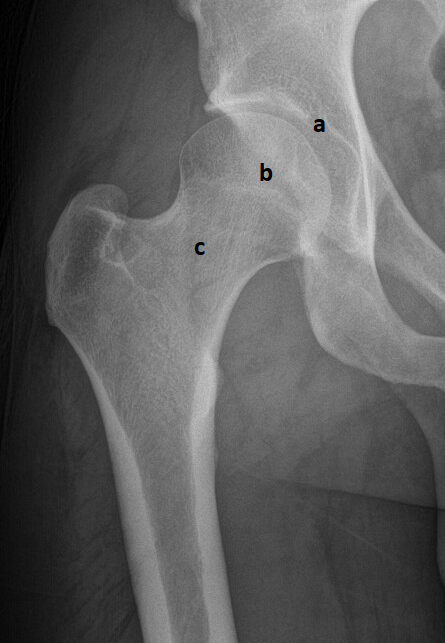

Totální endoprotézou (TEP) kyčelního kloubu se rozumí výměna nejen krčku a hlavice femuru, ale i implantace acetabulární komponenty kloubu (neoacetabulum) (obr. 3). Tím se liší od tzv. cervikokapitální (CKP) náhrady, u které je ponecháno acetabulum bez ošetření. Základní anatomii shrnuje obrázek 1.

Obr. 1a–c Anatomie zdravého kyčelního kloubu

a) kloubní jamka, b) hlavice stehenní kosti, c) krček stehenní kosti.

Zdroj: Ortopedická klinika FZS UJEP a MNUL.